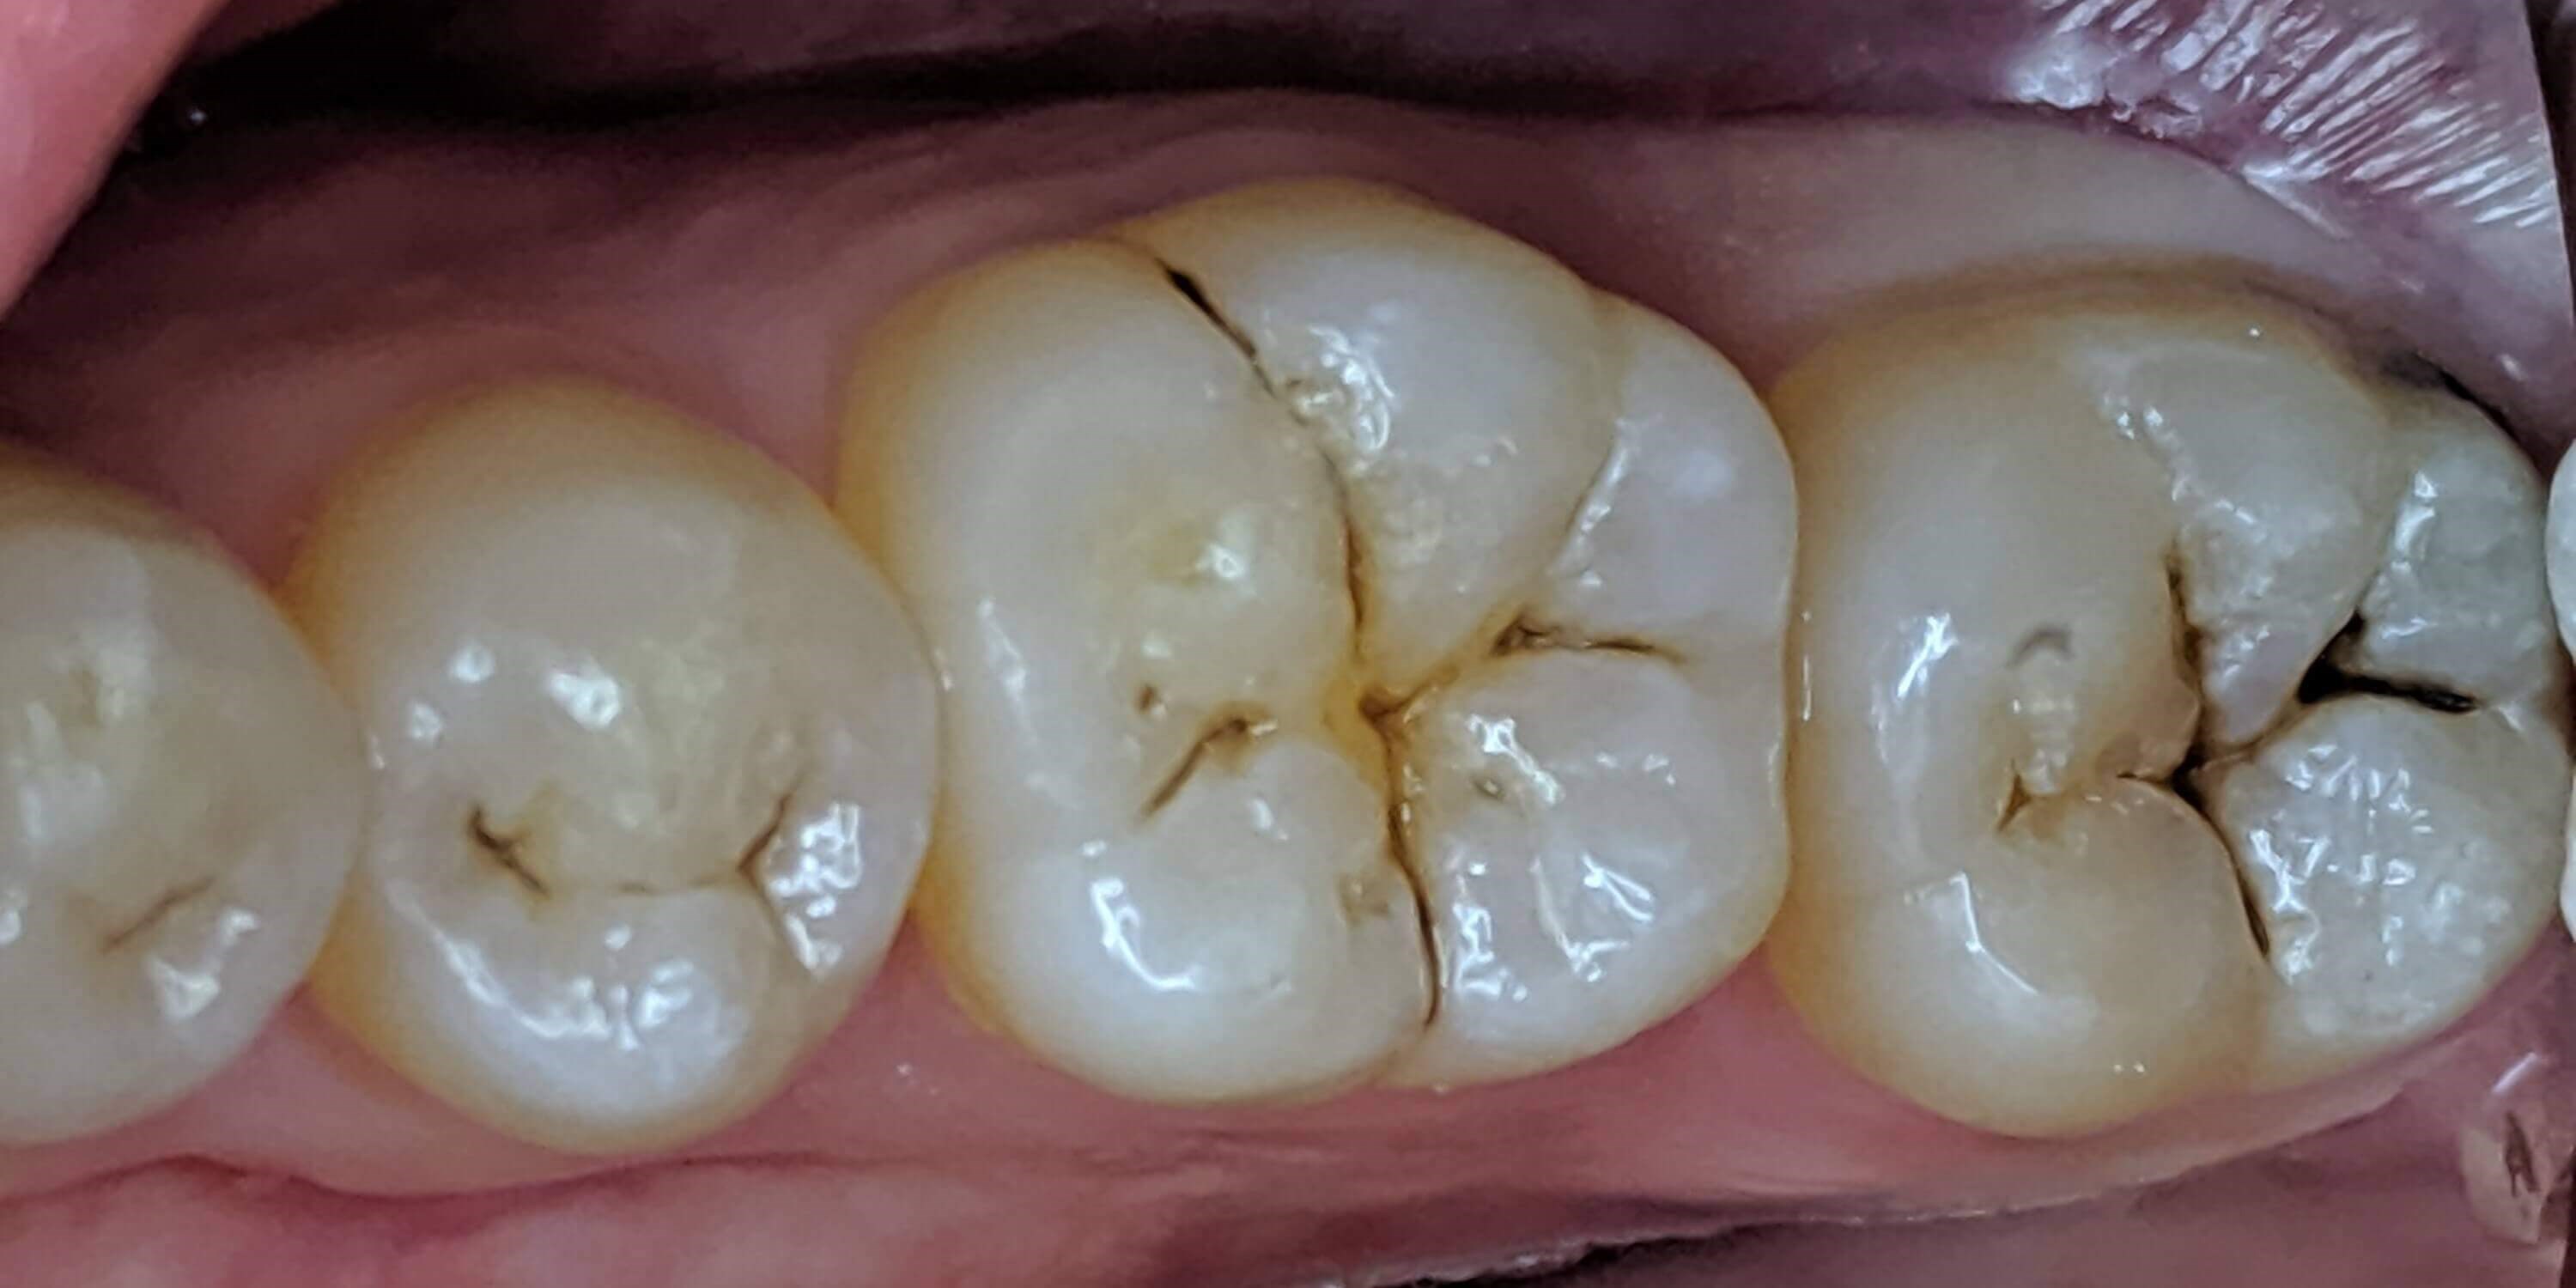

Tooth-colored fillings often fill in the decay in the enamel after it has been cleaned. Composite resin is a versatile material that can be used to treat other problems with your teeth, including cracks or enamel that has been worn down by teeth grinding (bruxism). Since the composite resin is colored to match your natural teeth, tooth-colored fillings can be used on both the front and back teeth for a seamless appearance. If you have metal fillings, talk to Dr. Kim or Dr. Chang about having them removed and replaced with tooth-colored fillings.

Getting a filling at Luminous Dental Studio is typically an easy process. The area surrounding the cavity will be numbed with a local anesthetic to minimize your discomfort. Other forms of sedation can be discussed if you have any fears or dental anxieties to help keep you at ease during the procedure. Once you are prepared, the decayed enamel is removed with a unique dental drill that Dr. Kim or Dr. Chang will select based on where the cavity is located in the tooth and the level of decay. After the enamel is removed and the tooth is cleaned, the cavity will be filled with the composite material and set with a special light. Dr. Kim or Dr. Chang will polish the filling so it feels comfortable and matches your natural teeth.